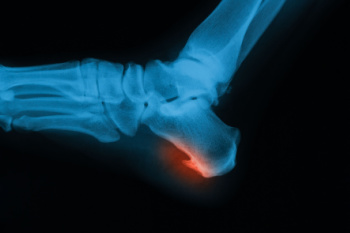

Bone spurs in the feet, also called osteophytes, form when the body produces extra calcium in response to stress, friction, or inflammation. These growths are not always painful, but they can interfere with nearby tissues and cause discomfort. Heel spurs are one of the most common types. They develop beneath the heel bone from strain on the plantar fascia or at the back of the heel due to tension from the Achilles tendon. Tarsal spurs occur in the midfoot, either on the top or bottom, and often make wearing shoes painful because of pressure against the spur. Toe joint spurs typically affect the big toe, leading to stiffness, limited motion, and pain while walking, especially when arthritis is present. A podiatrist can determine the cause of the bone spur, relieve pressure on surrounding structures, and recommend treatment. If you are experiencing foot or heel pain, it is suggested that you schedule an appointment with a podiatrist for an exam and appropriate treatment.